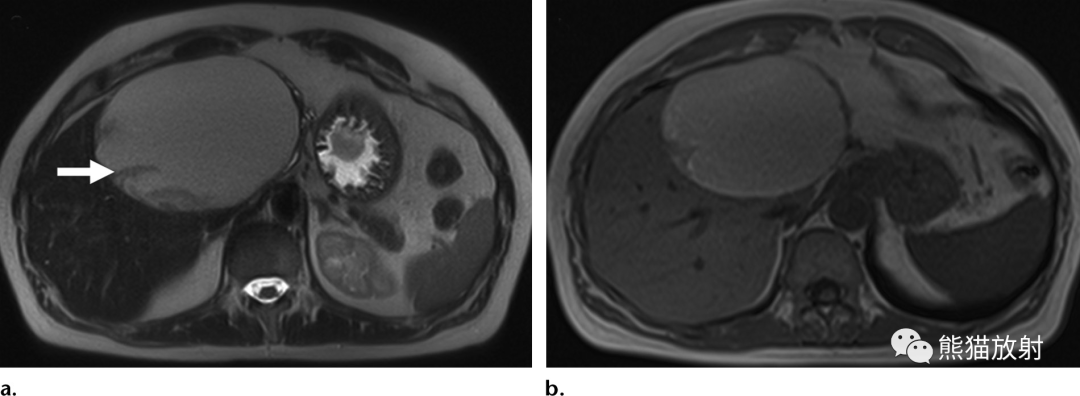

肝包虫囊肿与囊性肝肿瘤。

(a,b)49岁女性,肝包虫囊肿,表现为腹部肿块。(a) T1WI同相位图像显示低信号囊性肝脏病变伴分隔(箭头)。(b)对比增强延迟期图像显示囊内和低信号间隔无强化(箭头)。

(c,d)57岁女性,胆管囊腺瘤。(c)T1WI同相位图像显示分叶状囊性肝脏病变伴内部分隔(箭)。(d)对比增强脂肪抑制T1WI显示不规则中度强化的内分隔(箭),这有助于与包虫囊肿鉴别。

图片

51岁女性,酷似棘球蚴病的出血性肝囊肿,表现为急性上腹痛。(a)T2WI显示一个大的肝囊肿,具有中等信号强度和低信号波状带影(箭),类似分离的膜。(b) T1WI显示囊肿内高信号,与出血内容物一致。棘球蚴囊肿合并出血极为罕见,故而是一种可能性很小的诊断。